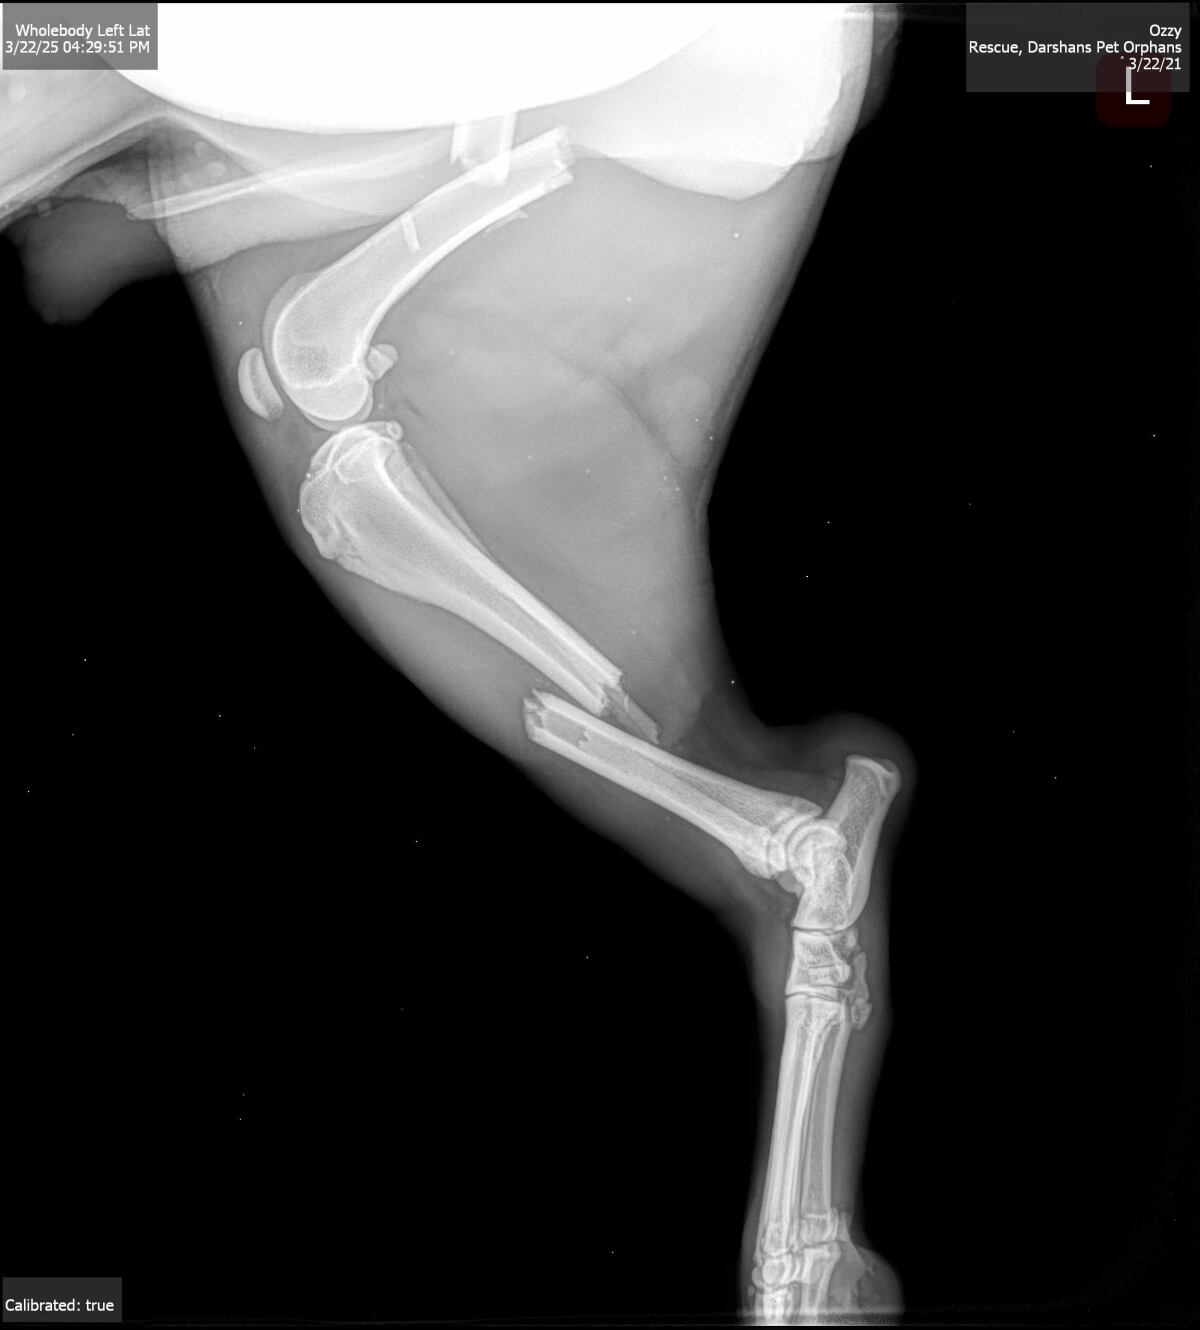

He had suffered for days with multiple fractures. He has two badly broken legs. His surgeries will be costly and not without risk of infection due to hardware placement. But Oreo has shown us he WANTS TO LIVE. He wags his tail in his kennel, despite his severe pain he must be in.